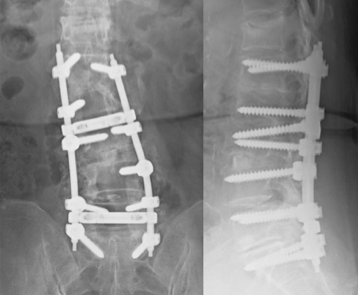

傳統手術需要一個至少8到10公分的傷口,若狹窄的椎節不只一節,傷口還會更大。由於椎管狹窄的原因相當多,壓迫神經的可能是增厚的黃韌帶、變形的小面關節、骨刺、突出的椎間盤、甚至椎間滑脫等等,為了解決神經的壓迫,傳統手術採取「一網打盡」的方式,將所有可能壓迫的原因一次解決,也就是將脊椎後半部的椎板、黃韌帶、小面關節內側全部切除,讓神經組織完全減壓。

- 第三、椎間不穩定。為了達到一網打盡的目的,若切除過多的椎板及小面關節,使得脊椎的結構受到破壞,就可能影響到脊椎的穩定性而造成椎間滑脫;時間久了反而造成更嚴重的神經壓迫。